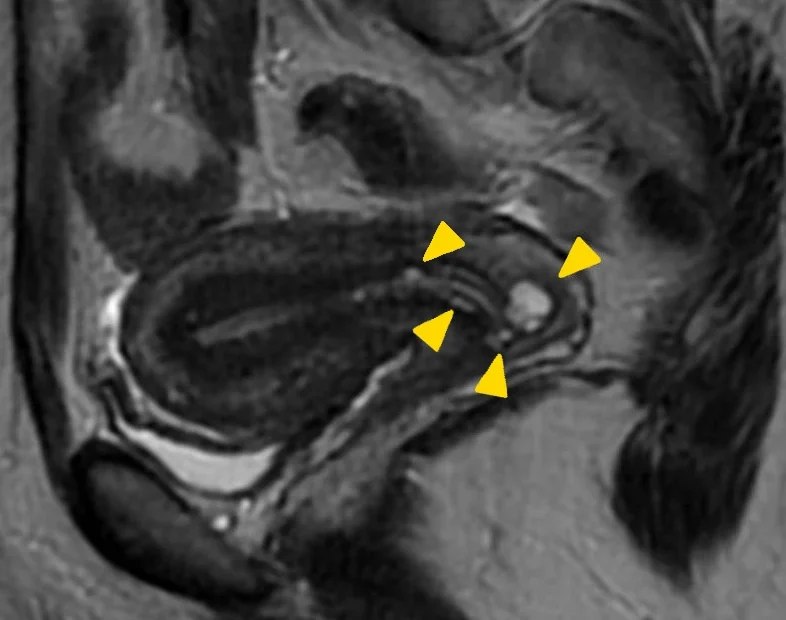

Submukozal miyomlar ve fertilite:

Submukozal miyomlar, döl yatağına yerleştiğinden doğurganlık üzerinde daha fazla etkiye sahip görülebilir. Bu tür miyomlar, implantasyonu engelleyebilir, gebelik sırasında komplikasyonlara olasıdır.

Miyomlar, doğurganlık üzerinde etkisi olabilecek faktördür. Büyümüş miyomlar uterus içindeki embriyonun implantasyonunu (yerleşmesini – yuvalanmasını) engelleyebilir, sperm ve yumurtanın buluşmasını zorlaştırabilir.